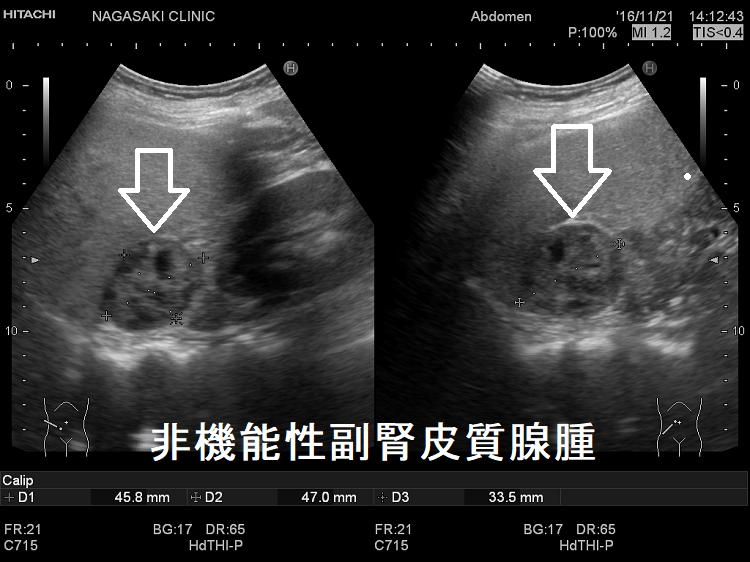

非機能性副腎皮質腺腫が3cm以上の場合、副腎癌(副腎原発1%/転移性5%)の事があります。

(右)非機能性副腎皮質腺腫:内部は不均一・粗で、当初、副腎癌か褐色細胞腫が疑われました。摘出標本で非機能性副腎皮質腺腫が確定。